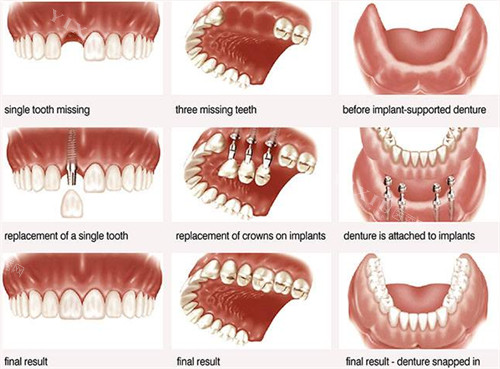

李伟医生在口腔领域深耕10多年,尤其擅长全口种植、即刻修复和智能化舒适种植。不少全口缺牙的患者找他,都说“李医生技术稳,种完牙当天就能吃软饭,疗养时间短”。

王舜医生从业10年以上,复杂阻生牙拔除、全口义齿修复是他的强项。前阵子有位大爷被智齿疼了半个月,王医生手法轻,5分钟就解决了,大爷直夸“没想象中可怕”。

要说艺星口腔的“招牌”,智能化种植牙必须排头一。医院用3D导板和CBCT设备,种牙位置精细到毫米,小切口操作减少创伤。适合单颗、多颗甚至全口缺牙的人。有位65岁的张阿姨,全口缺牙多年,李医生给她做了即刻种植,当天就能吃鸡蛋羹,现在啃苹果都没问题。